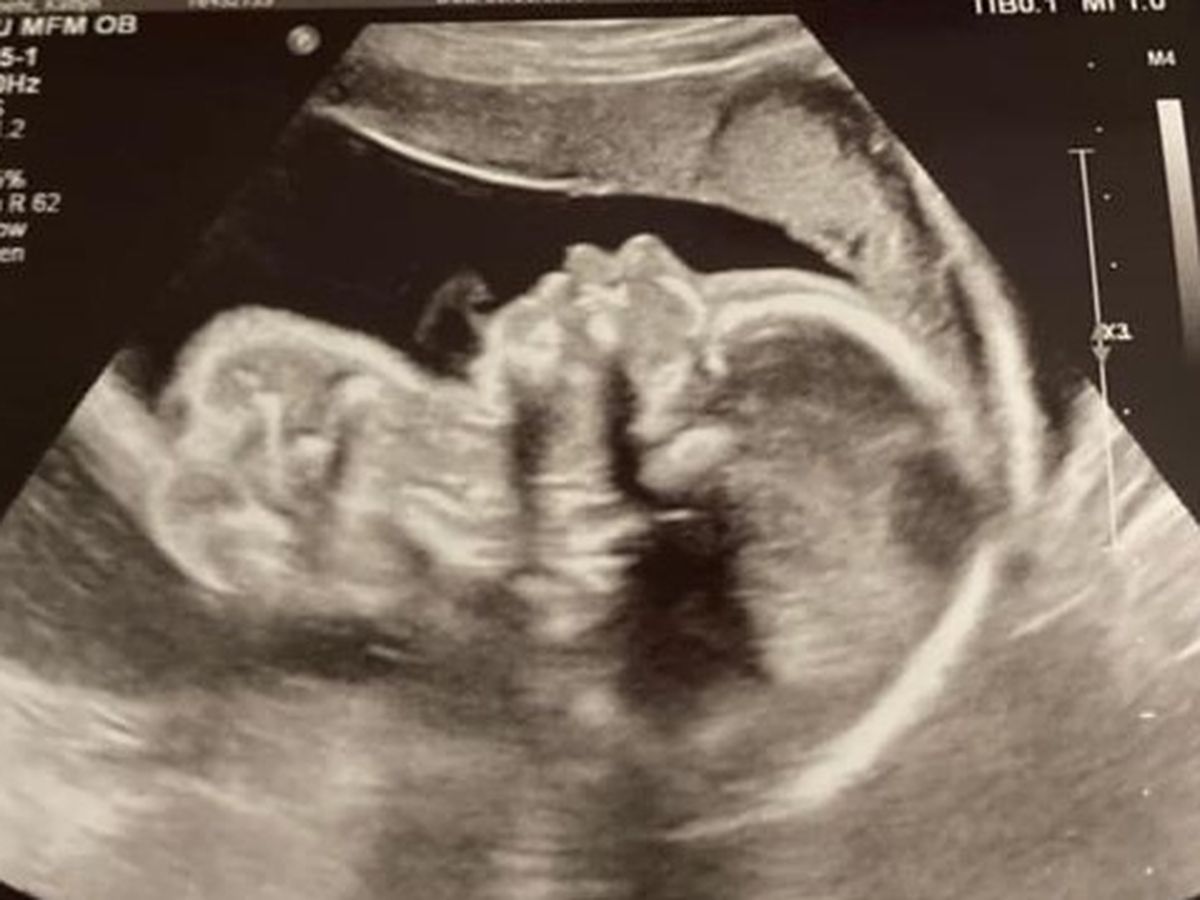

Katie & Corey Loehr- On April 7th my husband and I were on our way to our anatomy ultrasound, we were super excited to verify the gender and to see a detailed scan of our baby. All I can remember was being on cloud nine while looking at the ultrasound smiling from ear to ear in excitement. We got our ultrasound pictures of our sweet baby boy!! He was so tiny and perfect in every way, we kept laughing about how he was not shy to show off that he was a boy. The ultrasound tech left and said the doctor will be in to see you shortly, we were still talking about the pictures and his cute little hands and feet. Then the doctor walked in and said she wanted to double check the ultrasound tech; I didn’t think anything of it because I was just excited, I get another chance to see my baby. After about fifteen minutes the doctor told us she sees and abnormality with his heart. At this point my heart sank into my chest and the whole room got quiet. It felt as if the room had stopped for the rest of the ultrasound. She showed us a diagram of what a normal heart looks like and then showed us how underdeveloped one side of his heart was (Hypoplastic Left Heart Syndrome). Trying my best to listen through all the shock and tears she explained that his heart and stomach were also on the wrong side of his body, she said this was called Heterotaxy. At this point she told us she wanted to schedule an appointment with a pediatric cardiologist to verify and explain more. I just remember sitting in the car and my husband and I not saying a word the whole way home. Thoughts were racing. Is there anything I have done to cause this? Did I do something before I knew I was pregnant? Can I change the diagnoses? What is the outcome? Will my baby be okay? We had to wait about a month for him to get a little bit bigger before seeing the cardiologist, that was the longest month of our lives. After meeting with this specialist from Riley she did verify that he has HLHS and Hetrotaxy. Hypoplastic left heart syndrome (HLHS) is a congenital birth defect that affects the left side of the heart, leaving it under-developed and unable to pump oxygenated blood through the body. The left ventricle of the heart is too small in patients with HLHS, leaving the right ventricle to do all the work. HLHS typically requires three reconstructive surgeries to redirect the blood flow: the Norwood (which he will have 4 to 10 days after he is born), Glenn (he will have when he is 3 to 6 months old) and Fontan procedures (which he will have when he is 3 to 5 years old). One of the rarest and more severe heart defects is hypoplastic left heart syndrome (HLHS), which affects about 2 to 3 percent of babies born with a congenital heart defect. Heterotaxy syndrome is a condition in which some of the organs of the body are not located in their correct positions and some organs have not formed normally. Some children with heterotaxy syndrome have complicated congenital heart disease and need heart surgery. Some need abdominal surgery, and some do not have a spleen. Soon after we found out about his condition, we began our journey of multiple appointments, and stressful nights. I am Currently 31 weeks pregnant and we have had our ups and downs between me being sick and small complications during this pregnancy. He is being monitored very closely by some amazing doctors. We have met with a fantastic team up at Riley and are very hopeful of the outcome. I will be induced September 1st and then he will have his first open heart surgery 4 to 10 days after he is born. He will have a total of three surgeries, each surgery will repair his heart a little more. He will be in the intensive care unit for up to 6 weeks after his surgery hopefully less. Currently, he is super active and likes to kick mom all day and especially at night! We are excited to meet our bundle of joy; we have a long road ahead and ask for as many prayers as we can get!